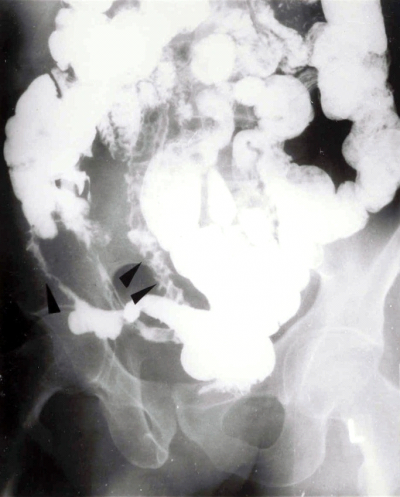

האבחון הרנטגני הוא חשוב. צילום בליעת בריום, אנטרוקליזיס וטומוגרפיה ממוחשבת של הבטן עם בליעת חומר ניגוד הם הכלים העיקריים לאבחנה. קשת של סימנים מצביעה על פתולוגיה במעי הדק.

- הסימן האופייני הוא ה-String sign, המבטא התעבות של דופן המעי והיצרויות של נהור המעי (תצלום 14.4).

- המעי מורחב.

- הדופן מעובה, ולכן המרחק בין הלולאות הוא רב (תצלום 15.5).

- המעי נוקשה - Lead pipe (תצלום 16.4).

- הרירית מאבדת את המבנה הרגיל שלה ואפשר לזהות בה פיסורות, תבנית אבני מרצפת, חריגויות ואי-סימטריה (תצלום -17.4 ו-18.4).

- נצורים אפשר להדגים בחלק מהמקרים (תצלום 19.4)

- Skip lesions הם סימן אבחנתי חשוב ביותר, שכן הם מבטאים קטעים נגועים יחידים לאורך כל המעי, ובכל קטע כזה נמצא את המאפיינים הרנטגניים של מחלת קרוהן